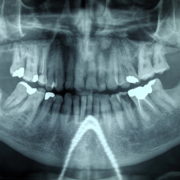

Cos’è l’Ortopantomografia?

Con il termine ortopantomografia si intende quell’esame radiografico che ci permette di vedere entrambe le arcate dentarie in una sola radiografia. Continua a leggere